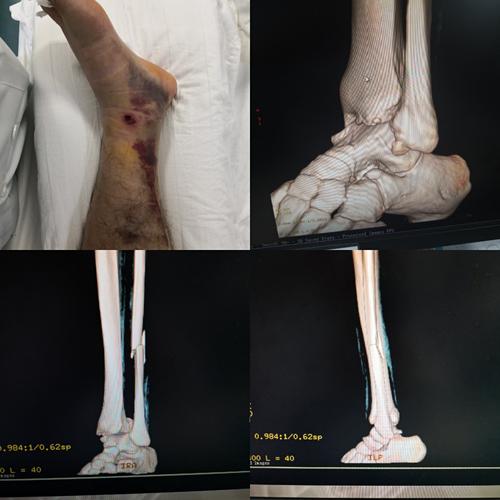

甘肃省人民医院骨一科杨青山副主任医师团队:踝关节骨折

左踝关节骨折

右踝关节骨折